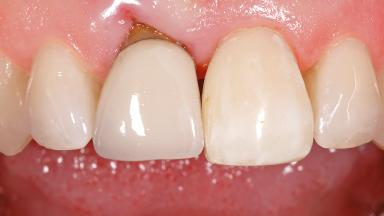

Early Placement of an Implant in a Maxillary Right Central Incisor Site

This 41-year-old female patient was referred to the clinic for the replacement of the right central incisor, since the tooth had developed a root fracture in the long axis that made extraction necessary. The healthy, non-smoking patient was first seen with the tooth still in place. A detailed Esthetic Risk Assessment was performed.The patient was worried about her dental esthetics and had high expectations for a successful treatment outcome from an esthetic point of view. The patient had a medium lip line that displayed parts of the gingiva in the anterior maxilla upon smile.

| Abutment Type | Customized |

| Prosthesis Type | FDP |